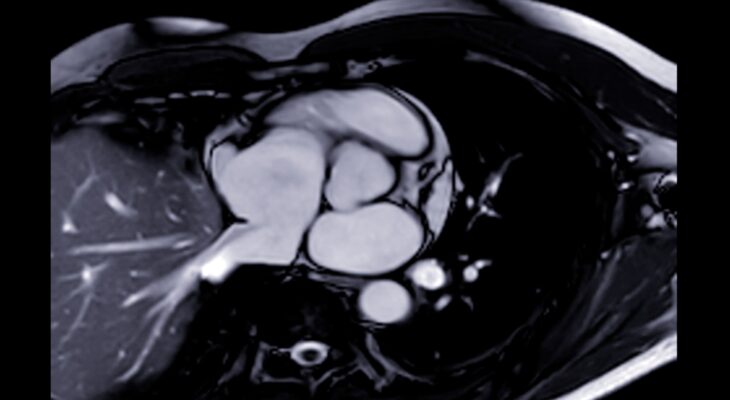

Plaučių embolijos priežastys ir rizikos veiksniai

Plaučių embolija – tai rimta būklė, kai į plaučių arteriją ar jos šakas patenka ir ją užkemša svetimkūnis. Dažniausiai tai ...